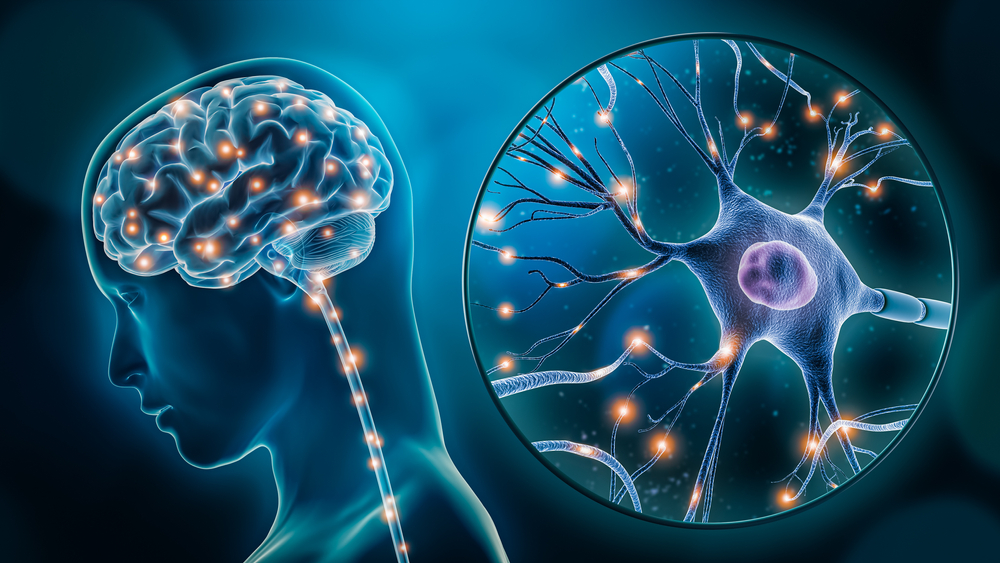

Складна для розуміння, але одночасно цікава та таємнича наука нейроімунологія спеціалізується на метаболічних та мітохондріальних хворобах. Їхній патогенез включає певні порушення в нервовій, імунній, ендокринній та багатьох інших системах організму. В процесі діагностики та лікування таких захворювань спеціалісти використовують дані найновітніших наукових досліджень. Місцем, куди можна звернутись людині, що має патології із нез’ясованою етіологією, є клініка нейроімунології VIVERE.

Сфера роботи клініки нейроімунології є досить широкою і включає розлади аутистичного спектру, PANDAS-синдром, епілепсію, а також депресивні та тривожні розлади, нейроінфекції, аутоімунні енцефаліти та багато інших патологій у дітей та дорослих людей. Звертатись до спеціалістів варто із наступними симптомами:

При зверненні із подібними проблемами, люди часто чують одну відповідь – причина захворювання є невідомою, тому і лікування не існує. Але в сучасних клініках діагностика знаходиться на дуже високому рівні, а знання спеціалістів є набагато глибшими. Для виявлення рідкісних захворювань та розуміння їх причини проводять пошук антитіл до специфічних рецепторів, а також інші лабораторні та інструментальні дослідження.